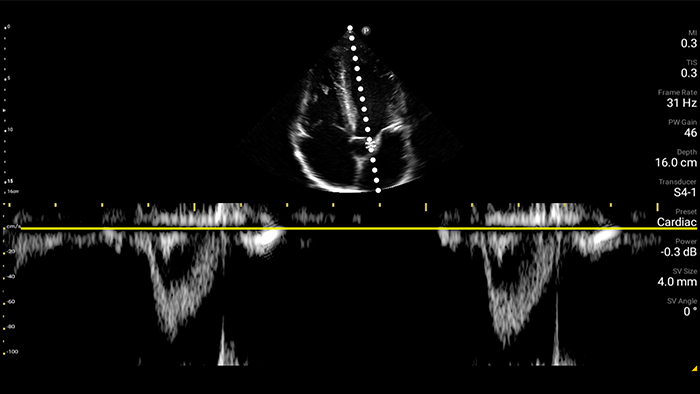

Respond fast with whole-body imagery

Lumify can help you assess patients from head to toe, whether it’s plantar fasciitis, tendonitis or bursitis in the patellar tendon, or even shoulder instability in the rotator cuff.

Lumify C5-2 broadband curved array transducer

• 5 to 2 MHz extended operating frequency range • 50mm radius of curvature • 2D, color Doppler, M-mode, advanced XRES and multivariate harmonic imaging, SonoCT • High-resolution imaging for deeper applications: abdominal, gall bladder, OB/GYN and lung imaging preset optimizations